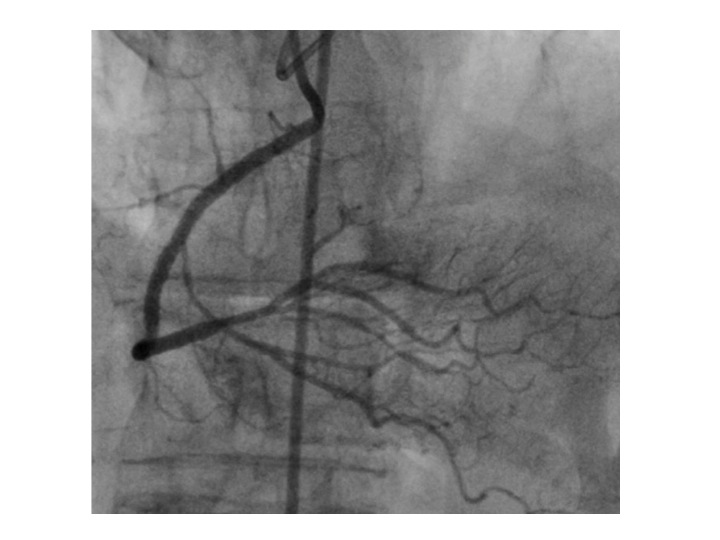

After beginning medical treatment with atorvastatin, carvedilol and acetylsalicylic acid the patient presented only a slight improvement, so we decide to add clopidogrel and perform a percutaneous revascularization of the total chronic occlusion. Angioplasty was successfully performed (Figures 4-6), with the implantation of two everolimus DES (drug-eluting stents). The patient had a good clinical evolution with total disappearance of the symptomatology.

Figure 4 Coronary angiography showing chronic total occlusion of proximal right coronary artery with the coronary wire.